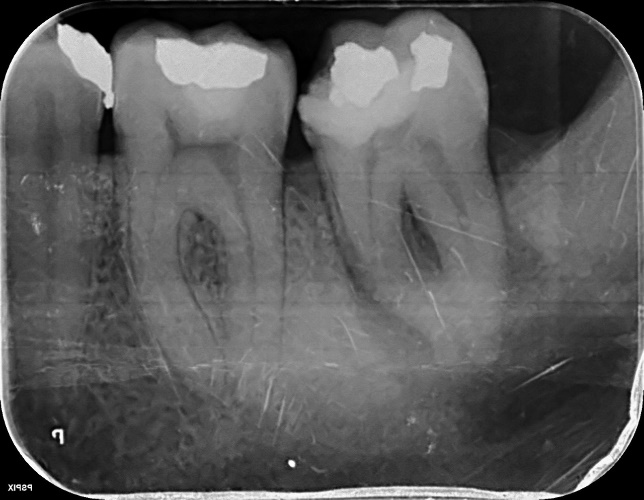

Lower Molar and premolar Primary root canal treatment